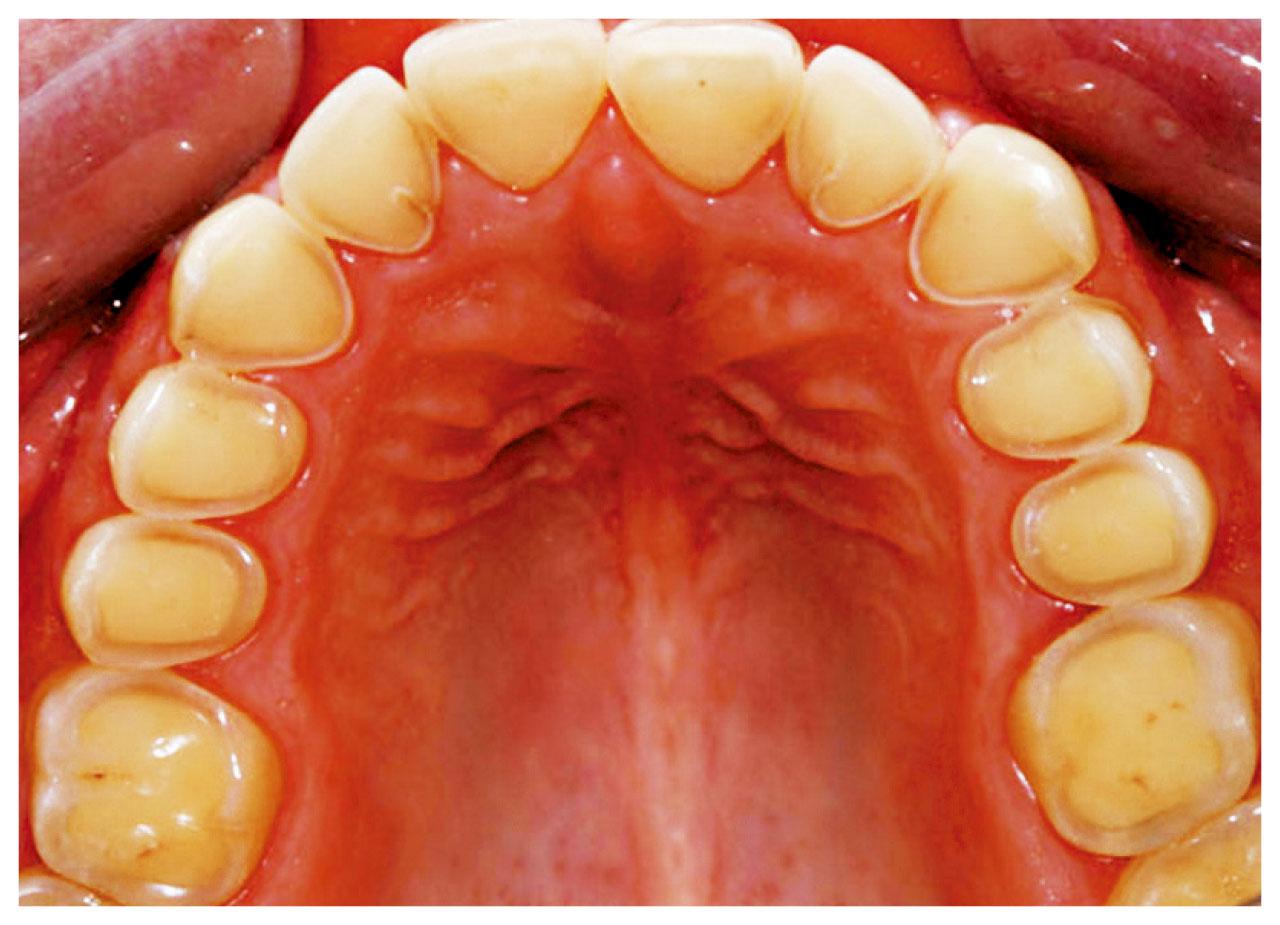

當琺瑯質變薄,便會透出偏黃色的象牙質。

初期牙齒侵蝕未必有明顯徵狀,但如情況惡化,或出現牙齒凹痕、變黃、敏感、蛀牙等,由於象牙質比琺瑯質較易被侵蝕,或使剩下的琺瑯質失去支撐,變得脆弱容易咬崩,嚴重影響日常生活。黃凌旻於臨床上遇過更嚴重情況,「除了牙齒表面的損耗外,牙房亦已收縮,並形成牙房結石,本屬人體自我保護機制,但結石或影響牙房的供血情況,可使牙神經慢慢枯死、牙齒容易受到感染。」